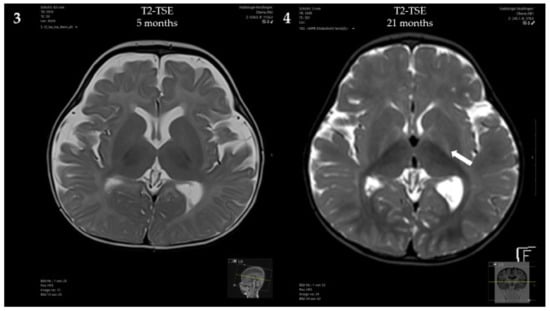

At 5 months, a brain MRI revealed mildly delayed myelination, dilated inner and outer cerebrospinal fluid spaces and mild periventricular diffusion interference (Figure 2). Clinically, the patient showed mild, predominantly motor, developmental delay (no hand support possible in prone position; no age-appropriate head posture; no turning of the child in prone and/or supine position) and mild muscular hypotonia. From 5 to 8 months of age, weight stagnation—likely due to decreased caloric intake—was observed. Dietary adaptation with an age-adequate calorie intake resulted in catch-up growth and normal weight at 14 months of age. Psychomotor development and muscle tone normalized.

Figure 2.

Brain MRI of the patient: (1,3) At 5 months, showing mildly delayed myelination, dilated inner and outer cerebrospinal fluid spaces and mild periventricular diffusion interference; (2,4) At 21 months, showing progressive diffusion impairment.

Psychomotor development at the age of 21 months was age-appropriate, and the patient showed normal growth under the Met-restricted diet (25 mg Met/kg/day). Met concentrations remained below 600 μmol/L. The concentration of AdoMet was normal (95.9 nmol/L, reference range 71–118 nmol/L). Despite the lack of neurological symptoms, a brain MRI at 21 months showed progressive diffusion impairment, but no structural abnormalities.